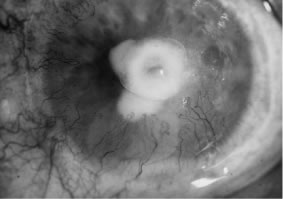

In the early stages of infection, filamentous fungi produce signs that are readily distinguishable from yeast or bacterial keratitis. The most distinctive sign is the presence of delicate, fine, feathery, opalescent, gray-white or yellow-white material in the anterior stroma, surrounded by scant cellular infiltrate or edema (Fig. 1). The epithelium may be intact. The overlying epithelium may be granular and the surface elevated and irregular in contour. Linear infiltrates typically extend into the adjacent stroma. Multiple discrete opacities may develop outside the perimeter of the principal focus of inflammation, either separated by clear stroma or linked by fine linear collections of inflammatory cells and material (Figs. 2 and 3). In the absence of inflammation in the adjacent stroma, branching hyphal fragments may be visualized by biomicroscopy (Figs. 4 and 5). Confocal microscopy may also detect hyphal elements within the stroma.28,29 Peripheral infection resembles noninfectious marginal infiltrative and ulcerative keratitis (Fig. 6). Multifocal keratitis may develop after contact lens wear or injury by multiple projectiles (Fig. 7). In the early stages, iritis is present and the intraocular pressure remains normal. Inappropriate, empirical therapy of fungal keratitis with topical fluoroquinolone or aminoglycoside antibiotics may suppress or eliminate the superficial elements but allow extension of the organisms into the stroma because these agents may possess selective antifungal activity.4,30,31

There is no distinguishing clinical sign by which to recognize the genus or species of the infectious filamentous fungus. F. solani is the most virulent organism and typically produces rapidly progressive infection characterized by epithelial and stromal ulceration, dense stromal necrosis, abundant cellular infiltrate, and edema in the adjacent stroma and hypopyon (Figs. 8 and 9). Delicate feathery components are transient. Individual hyphal fragments are rarely visualized. Infection by certain species of Aspergillus and Scedosporium (Figs. 10 and 11) resembles F. solani keratitis and progresses rapidly. Infection by less virulent organisms, such as Curvularia and Alternaria species, produces small, focal (less than 3-mm diameter) areas of nonnecrotizing stromal inflammation with delicate feathery borders (see Fig. 1 and Fig. 12). Macroscopic pigmentation may develop in keratitis caused by Alternaria, Curvularia, and other dematiaceous fungi (Fig. 13).4,11,14 The central component may progress to dense, opaque, gray-white suppuration in the deep stroma without enlargement in total area and may be accompanied by mild inflammation in the adjacent stroma. Iritis is minimal to moderate. Infection caused by other, relatively less virulent organisms resembles herpes simplex or noninfectious keratitis (Fig. 14).